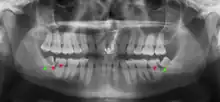

| Diagnostic method | Examination, x-ray |

Impacted wisdom teeth are classified by their direction of impaction, their depth compared to the biting surface of adjacent teeth and the amount of the tooth's crown that extends through gum tissue or bone. Impacted wisdom teeth can also be classified by the presence or absence of symptoms and disease. Screening for the presence of wisdom teeth often begins in late adolescence when a partially developed tooth may become impacted. Screening commonly includes a clinical examination as well as x-rays such as panoramic radiographs.

If the tooth cannot be assessed with clinical exam alone, the diagnosis is made using either a panoramic radiograph or cone-beam CT. Where unerupted wisdom teeth still have eruption potential several predictors are used to determine the chance of the teeth becoming impacted. The ratio of space between the tooth crown length and the amount of space available, the angle of the teeth compared to the other teeth are the two most commonly used predictors, with the space ratio being the most accurate. Despite the capacity for movement into early adulthood, the likelihood that the tooth will become impacted can be predicted when the ratio of space available to the length of the crown of the tooth is under 1.[5]: 141